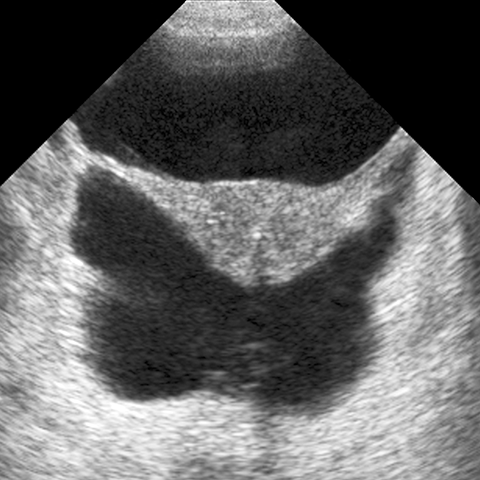

Transabdominal Ultrasound [4 of 5]